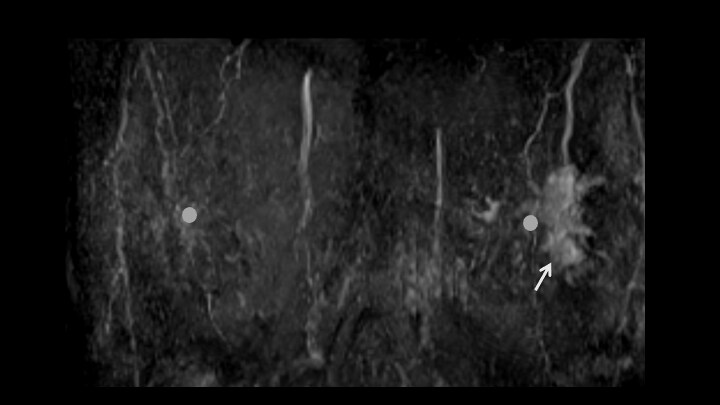

1. ダイナミックMRI 早期相MIP画像(正面)

造影後MIP画像では病変の分布、乳頭との位置関係が把握しやすい(矢印)

5. ダイナミックMRI 早期相

左乳頭外側にnon-mass enhancementを認める(矢印)

8. ダイナミックMRI 後期相

早期相と同様に左乳頭外側にnon-mass enhancement。